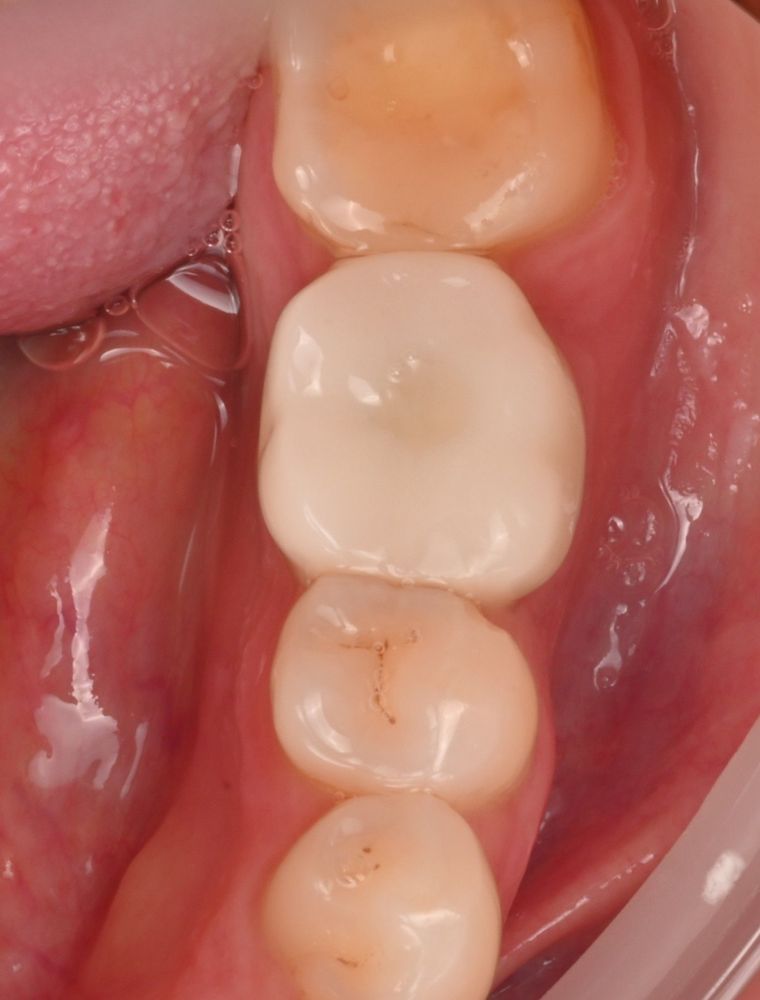

We chose a staged approach. First, the tooth was carefully removed, allowing the tissues to heal naturally. After about six weeks, the implant was placed using precise digital planning. A temporary crown was then fitted to shape a natural gum contour, followed by the final permanent crown.

The tooth was fully restored. The implant is stable, the gum looks natural, and oral hygiene is comfortable. The patient returned to his normal life with a reliable, long-term solution.